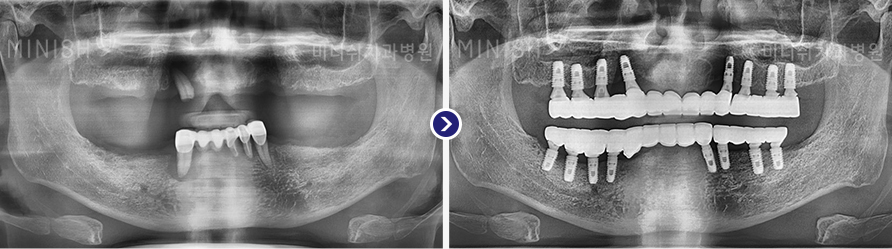

种植牙前后变化

01 X光片